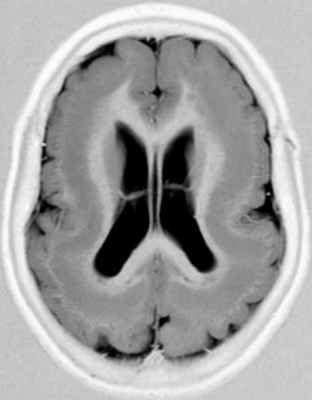

• Гипертрофированное БВ часто имеет гиперинтенсивный сигнал на T2-ВИ/FLAIR (ускоренная миелинизация)(а) На рисунке коронального среза показано увеличение объема большого полушария головного мозга вследствие его чрезмерного роста. Обратите внимание на смещение срединных структур, избыточное количество белого вещества (БВ), утолщение и сглаженность/дисморфизм извилин, а также аномальную конфигурацию ипсилатерального переднего рога.

(б) Бесконтрастная КТ, аксиальный срез: у четырехлетней девочки с некупируемым судорожным синдромом определяется увеличение правого большого полушария, ипсилатеральной 1 /2 мозгового черепа в сочетании с увеличением объема белого вещества лучистого венца, ипсилатерального мозолистого тела, а также свода мозга. Кроме того, отмечается латеральное смещение серпа мозга. (а) МРТ, Т2-ВИ, аксиальный срез: у того же пациента определяется увеличение размеров полушария в сочетании с повышением сигнала от его БВ, а также увеличение деформированного правого желудочка и утолщение диспластичной коры.

(б) МРТ, Т2-ВИ, корональный срез: определяются увеличение размеров правого полушария, а также латеральное смещение серпа мозга. Передний рог ипсилатерального бокового желудочка деформирован и заострен. Изменения соответствуют классической гемимегалэнцефалии (ГМЭ).в) Патология:

Гемимегалэнцефалия (ГМЭ) или унилатеральная мегалэнцефалия — дисплазия головного мозга, обусловленная унилатеральными нарушениями нейронной миграции и пролиферации, результатами которых является одностороннее диспластическое увеличение одной из гемисфер (В.А. Чадаев и соавт., 2003). Гемимегалэнцефалия может встречаться как изолированный порок, так и сочетаться с гемигипертрофией всего тела — синдром Клиппель-Треноне-Вебера (Anlar B. и соавт., 1988); нейрокожными синдромами: протеуса, линейного невуса, эпидермального невуса, гипомеланоза Ито, нейрофиброматоза, туберозного склероза (De Lone D.R. и соавт., 1999; Sasaki M. и соавт., 2000).

Облигатным признаком ГМЭ является чрезмерное развитие одной гемисферы при нормальных размерах другой. Нарушение устройства рисунка извилин (сулькации) может быть представлено участками коры с увеличенными, утолщенными (пахигирия) или удлиненными и истонченными (полимикрогирия) зонами. В гипертрофию обычно вовлекаются глубинные структуры полушарий, реже мозжечок. Гемигипертрофия ствола мозга или спинного мозга является редкостью (Tuxhorn I. и соавт., 1997). Диспластические нарушения могут обнаруживаться и в контралатеральном «здоровом» полушарии.

Диагноз ГМЭ в современных условиях устанавливается, в подавляющем большинстве случаев, при МРТ исследовании головного мозга. МРТ у больных с ГМЭ выявляет асимметрию гемисфер за счет диффузно увеличенного, аномального полушария. Характерна вентрикуломегалия диспластичной гемисферы. В Т2 — режиме выявляется интенсивный сигнал в белом веществе — результат сочетания глиоза и участков гипомиелинизации.Материал и методы. Нами обследовано 4 больных ГМЭ в возрасте от 5 до 7 лет; 2 мальчика и 2 девочки (табл. ). Проводилось неврологическое обследование, рутинная ЭЭГ, видео – ЭЭГ мониторинг с включением сна (6-12 часов исследования), магнитно – резонансная томография (МРТ) с напряженностью поля 1,5 Tsl. Целью исследования было изучение клинических, электроэнцефалографических и нейровизуализационных характеристик больных гемимегалэнцефалией. Особое внимание уделялось характеристики симптоматической фокальной эпилепсии при ГМЭ: возраст дебюта приступов, их характеристика, динамика течения.

МРТ исследование было ведущим в верификации синдрома ГМЭ.